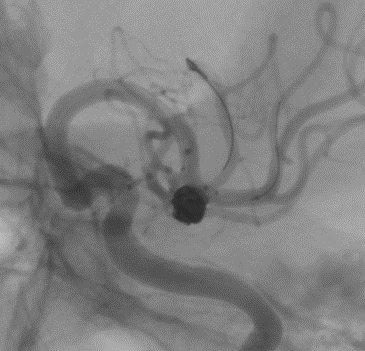

En este aneurisma se realizó la cateterización con dos balones de remodeling Eclipse 2L con microguías Traxcess y Ashahi .014, realizando dos cambios de curva para el cateterismo distal. El acceso proximal se realizó con un introductor largo Ballast .088 de 90cm que permite el uso de dos balones y un microcatéter para introducir los coils.

Con un buen posicionamiento de los balones se logró el cierre completo del aneurisma con seguridad y control garantizando la permeabilidad de las ramas. En este caso no se completó el tratamiento con stent por que la paciente debe someterse a una cirugía reciente.